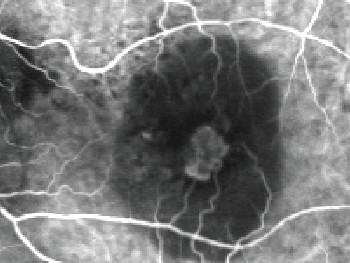

A Angiografia Fluoresceínica (AF), ou Angiofluoresceinografia, é um exame de grande importância no estudo das doenças que atingem a retina, coróide e nervo óptico. Doenças como Retinopatia Diabética, Degeneração Macular Relacionada à Idade (DMRI), Degenerações retininas hereditárias, Doenças oclusivas vasculares, entre outras, têm indicação para realizar esse exame, que apesar do nome complicado, é relativamente simples em sua realização, porém necessita grande experiência na área de retina e vítreo para a sua interpretação.

O HRA-2 da Heidelberg Engineering permite captção de alta resolução de filmes e fotos. Além disso pode ser realizado simultaneamente ao exame de indocianina verde.